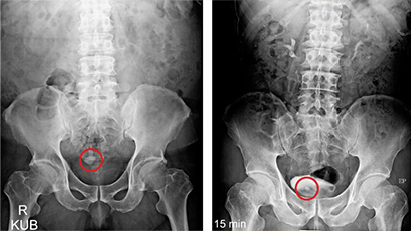

01방사선 검사는 X-ray 촬영을 통해 신장, 요관, 방광을 검사합니다.

신장결석, 요관결석, 방광결석 등

04결석이 의심되는 경우

방광결석